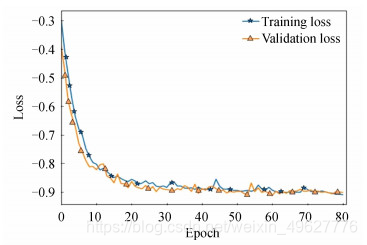

图 9和10分别为结合实例归一化网络收敛示意图和脑肿瘤测试集Dice指标分布图.对比图 7(b)和图 9可知,结合了实列归一化的脑肿瘤检测网络收敛速度更快,训练集和测试集的损失值曲线拟合程度良好,表明实列归一化的方法不仅能够加快网络的收敛速度,同时也缓解了多模态脑肿瘤检测网络中存在的过拟合问题.

图 9 结合实例归一化网络收敛示意图